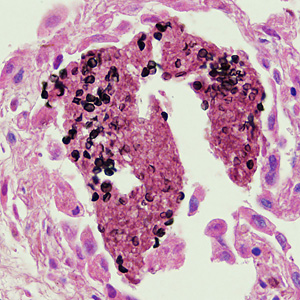

A 49-year-old man with AIDS was admitted to the hospital for complaints of a persisting fever and dry cough. A chest radiograph showed bilateral infiltrate. A sputum specimen was collected and stained with Giemsa, but no parasites were observed. A lung biopsy was obtained, sectioned, and stained with both methenamine silver and hematoxylin and eosin (H&E) stains. Figures A and B show what was observed at 500x magnification on one of the stained sections. What is your diagnosis? Based on what criteria?

Figure A